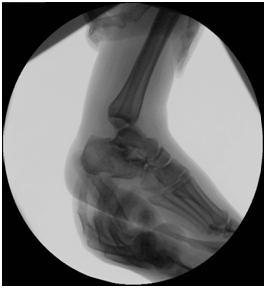

Treatment Management began with stabilization of the patient’s general condition, and later definite treatment on 2nd stages. 1st stage: Patient went for decompression spine surgery and examination under anesthesia (EUA) of the right ankle which demonstrated medial and lateral ligament complex instability as evident by a positive anterior drawer test (Figure 3), a posterior drawer test (Figure 4) and a positive varus and valgus stress tests with intact syndesmosis clinically (Figure 5 & 6). Because of the local swelling, the patient was put in a cast. 2nd stage: 5 days later, when the swelling subsided, patient underwent open reduction internal fixation of the right calcaneus fracture and repair of the medial and lateral ligament complex tears.

Figure 3 Anterior drawer test: an anteriorly directed force is applied to the heel while supporting the leg.

Figure 4  Posterior drawer test: a posteriorly directed force is applied to the foot while supporting the leg.

Figure 5 Varus stress test: Varus force is applied to the ankle. The ankle joint open up laterally.

Figure 6 Valgus stress test: Valgus force applied to the ankle. The ankle opens up medially.